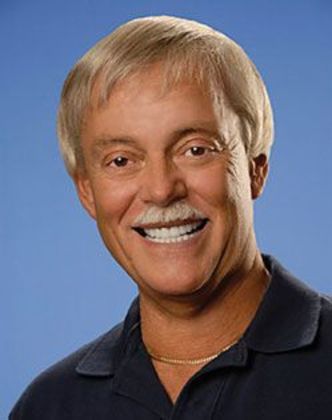

Full Mouth Rehabilitation: Bill

This patient wanted his smile to look better. He had a severe life long grinding habit that decimated his teeth, causing fractures, tooth loss and collapse of his bite. He wanted the best possible outcome. His was a complicated treatment that required the coordination of treatment of several specialists, much patience on his part, and resulted in an impressive result.